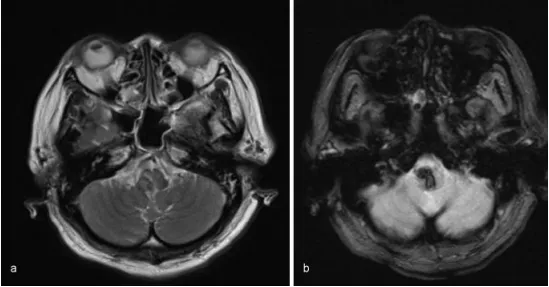

头晕、头痛、复视,当地医院检查怀疑脱髓鞘病变,治疗后又加重,前往北京进一步PET核磁检查考虑是低级别胶质瘤,建议穿刺活检后明确诊断。 常有患者和家属疑惑,现在的医学进步,为何...